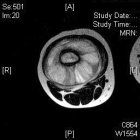

M.D. - 5 year old female with right thigh pain for one month, her parents have noticed swelling in her thigh over the past week, she began limping a few days ago and now is reluctant to bear weight on her right leg